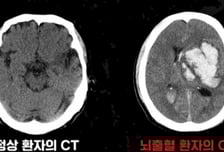

"망치로 내려찍는 듯한 두통" 고혈압 환자의 '이 증상' 골든타임도 없다

뇌에 갑작스럽게 타격이 가해지는 질환이 뇌졸중이다. 뇌졸중은 △뇌혈관이 막히는 '뇌경색' △혈관이 터지는 '뇌출혈'(출혈성 뇌졸중)로 나뉜다. 이 가운데 뇌출혈은 전체 뇌졸중의 약 20%를 차지한다. 뇌출혈은 전조 증상 없이 갑작스럽게 찾아오고 예후가 매우 나쁘다. 한번 발병하면 치료하더라도 후유증을 남길 수 있다. 빠른 인지·대처가 생명과 후유증을 좌우한다. 가천대 길병원 신경외과 김명진 교수는 "뇌출혈은 발병 즉시 치료해야 후유증을 남기지 않는다"고 설명했다. 뇌출혈의 가장 큰 원인은 '고혈압'이다. 혈압이 자연스럽게 오르내리는 정상 혈압과 달리, 고혈압은 혈관 벽에 지속해서 부담을 가해 손상을 입힌다. 이렇게 손상된 혈관은 점차 딱딱해지고, 신축성을 잃는다. 이 상태에서 순간적으로 혈압이 빠르게 상승하면 결국 혈관이 터지며 뇌출혈로 이어진다. 고혈압 외에도 혈관 일부가 꽈리처럼 부풀며 쉽게 파열되는 뇌동맥류, 선천적으로 혈관 구조가 비정상적인 뇌혈관 기형, 외상, 출혈성 질환,